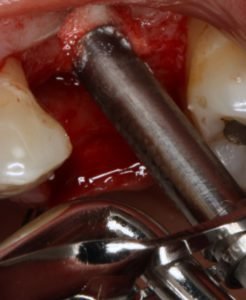

Figura 4: fresa neurológica do sistema SCA realizando a perfiração pela crista do rebordo;

Figura 5: aplicador de enxerto com Osteogen®

Figura 6: aplicador enxerto no alvéolo cirúrgico;